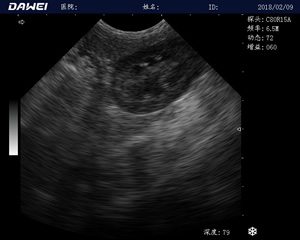

MT15獸用B超機適用探頭

適用對象:

牛羊馬豬犬貓及多種家禽、實驗動物、野生動物、及部分水生動物

應(yīng)用范圍:

中小動物的肝、膽,脾、腎、膀胱、子宮、妊娠等各組織器官的檢查和病變的診斷